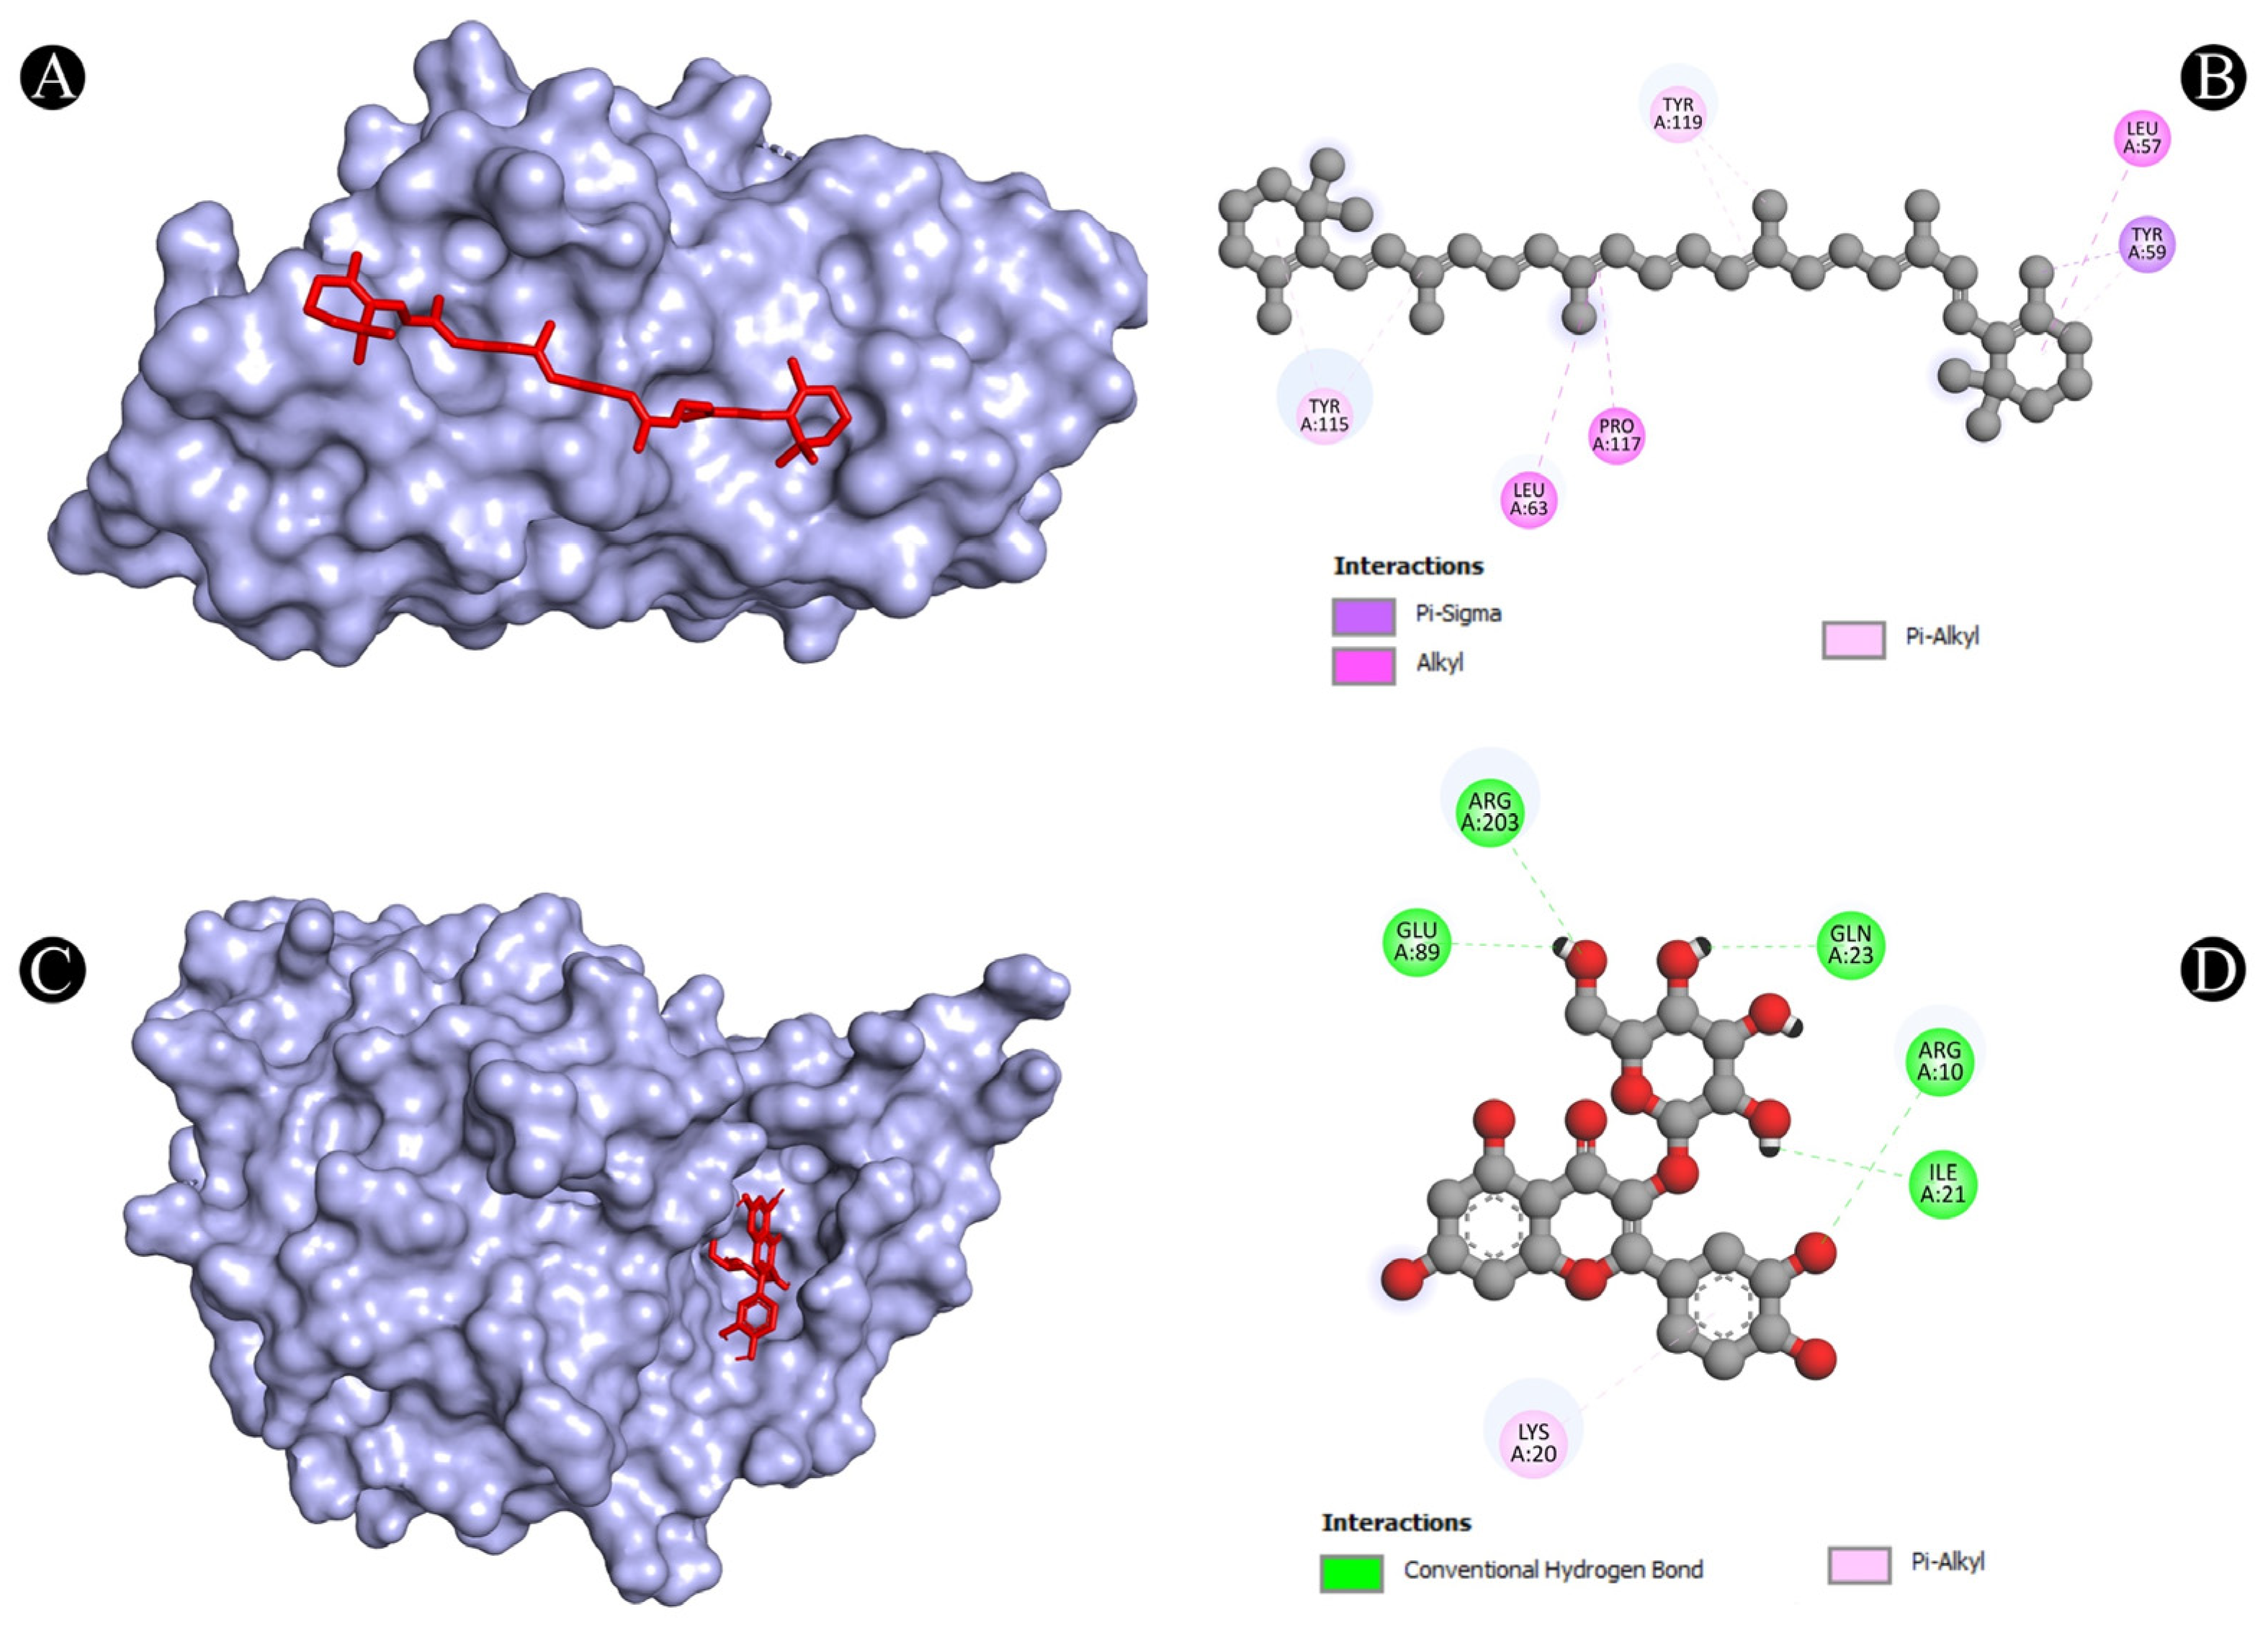

3.4. Molecular Docking Analysis

| 8 | TNF | N:UNK1:C-A:TYR59 | Pi-Sigma | 3.73712 |

| A:LEU57-N:UNK1 | Alkyl | 5.38917 | ||

| A:LEU63-N:UNK1 | Alkyl | 5.26338 | ||

| A:PRO117-N:UNK1 | Alkyl | 4.92982 | ||

| A:TYR59-N:UNK1 | Pi-Alkyl | 4.35802 | ||

| A:TYR115-N:UNK1 | Pi-Alkyl | 4.90592 | ||

| A:TYR115-N:UNK1 | Pi-Alkyl | 4.49189 | ||

| A:TYR119-N:UNK1 | Pi-Alkyl | 4.33167 | ||

| A:TYR119-N:UNK1:C | Pi-Alkyl | 4.13411 | ||

| 9 | TP53 | A:ARG10:NH1-N:UNK1:O | Conventional Hydrogen Bond | 3.15168 |

| A:ARG203:HH2-N:UNK1:O | Conventional Hydrogen Bond | 2.79577 | ||

| N:UNK1:H-A:GLU89:OE2 | Conventional Hydrogen Bond | 2.30967 | ||

| N:UNK1:H-A:GLN23:O | Conventional Hydrogen Bond | 2.28776 | ||

| N:UNK1:H-A:ILE21:O | Conventional Hydrogen Bond | 2.7139 | ||

| N:UNK1-A:LYS20 | Pi-Alkyl | 5.35537 | ||

| TNF (tumor necrosis factor) | Induces inflammation and cell death against fungal infection | TNF is a cytokine that can induce inflammation and cell death against fungal infection by activating the expression of genes such as NOS2, CXCL10 and ICAM1. TNF can also enhance the phagocytosis of fungal cells by macrophages and neutrophils. Ajwa date extract may stimulate the release of TNF and increase its anti-fungal function. | [78] |

| TP53 (tumor protein p53) | Induces the apoptosis (cell death) of infected cells and prevents fungal dissemination | TP53 is a protein that can trigger apoptosis, which is a process of programmed cell death, in response to DNA damage or stress. Apoptosis can help eliminate infected cells and prevent the spread of fungal pathogens. Ajwa date extract may stimulate the release of TP53 and increase its apoptotic function. | [93] |